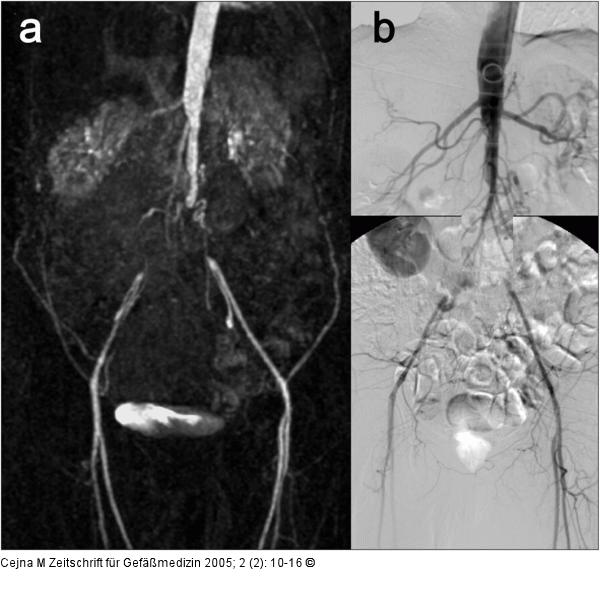

Abbildung 1: Leriche-Syndrom - MAR - DSA 47jähriger Patient mit Leriche-Syndrom, Vergleich zwischen MRA-Untersuchung (a) (obere Etage bei MobiTrak®, Untersuchungsdauer 25 Min., 30 ml Gadolinium) und transbrachialer i.a.-DSA (b) (Untersuchungsdauer 60 Min., zusammen 60 ml jodhältiges KM). Die Untersuchungen sind gleichwertig in bezug auf Beurteilung von Verschlußhöhe, Verschlußlänge und Anschlußgefäße. |

47jähriger Patient mit Leriche-Syndrom, Vergleich zwischen MRA-Untersuchung (a) (obere Etage bei MobiTrak®, Untersuchungsdauer 25 Min., 30 ml Gadolinium) und transbrachialer i.a.-DSA (b) (Untersuchungsdauer 60 Min., zusammen 60 ml jodhältiges KM). Die Untersuchungen sind gleichwertig in bezug auf Beurteilung von Verschlußhöhe, Verschlußlänge und Anschlußgefäße. |